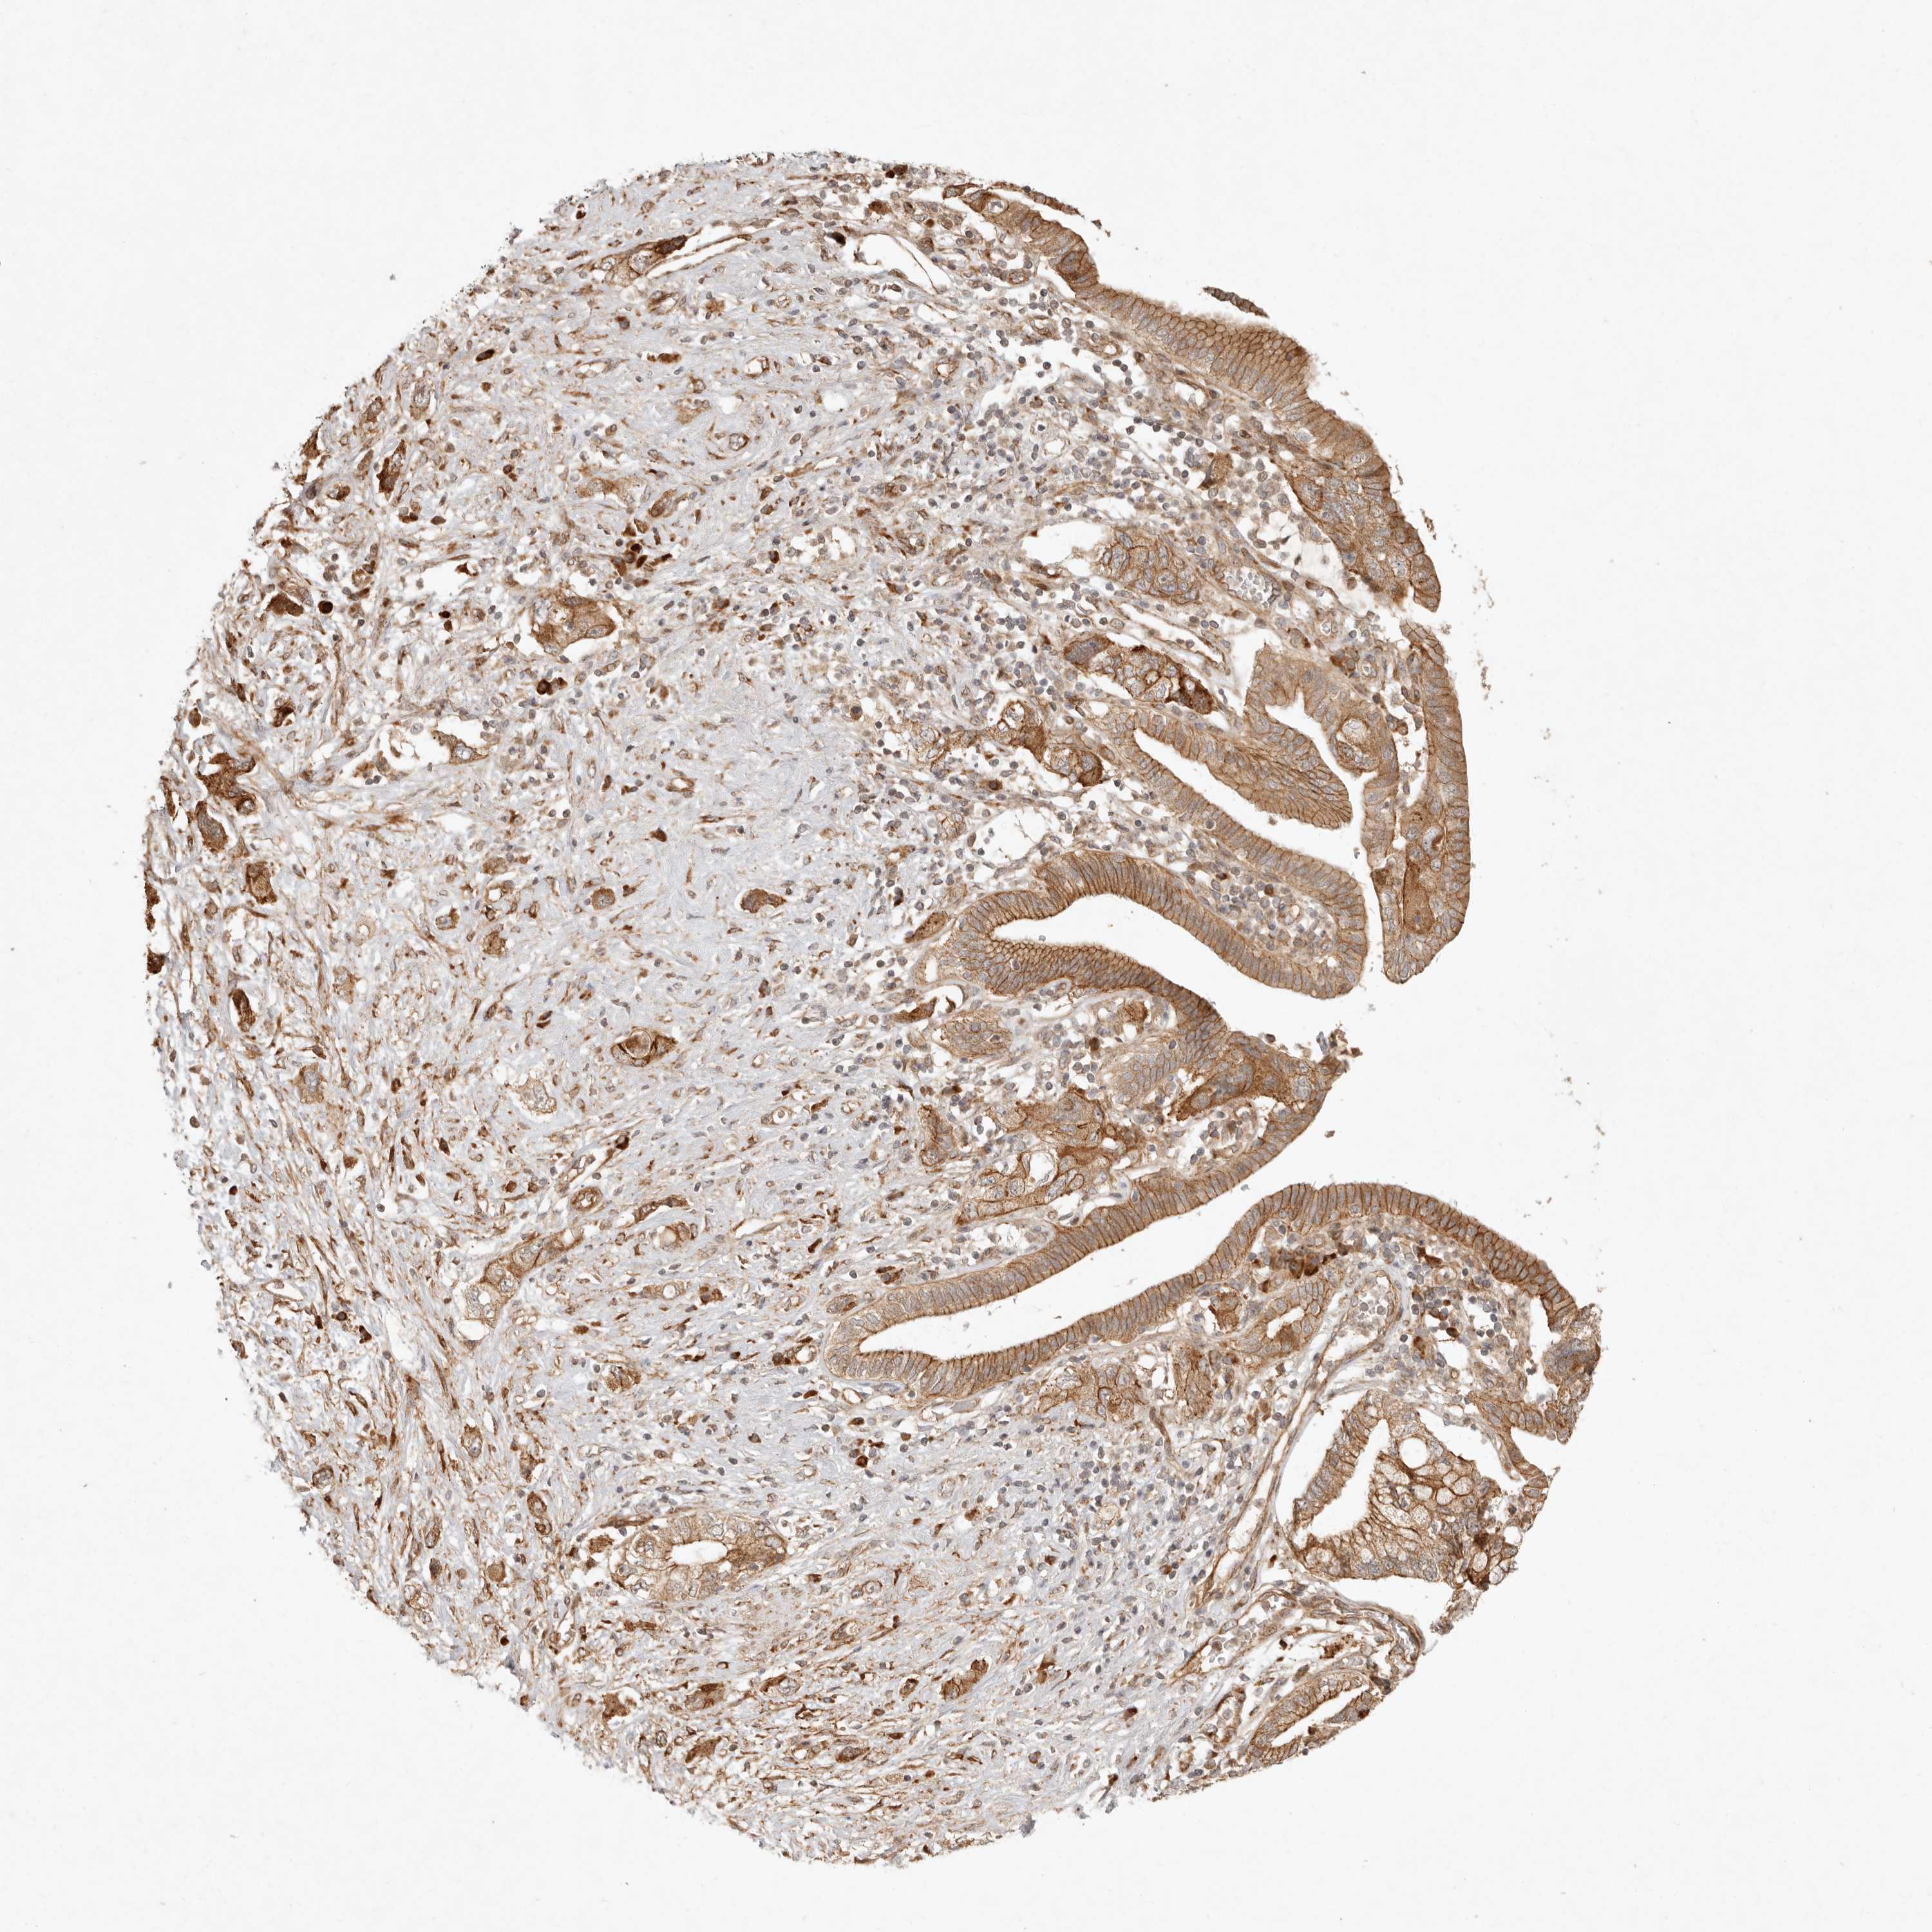

PANCREATIC CANCER - Protein expressioni

A mouse-over function shows sample information and annotation data. Click on an image to view it in a full screen mode. Samples can be filtered based on level of antibody staining by selecting one or several of the following categories: high, medium, low and not detected. The assay and annotation is described here.

Note that samples used for immunohistochemistry by the Human Protein Atlas do not correspond to samples in the TCGA dataset.

Antibody stainingi

Antibody staining in the annotated cell types in the current human tissue is reported as not detected, low, medium, or high, based on conventional immunohistochemistry profiling in selected tissues. This score is based on the combination of the staining intensity and fraction of stained cells.

Each image is clickable and will lead to virtual microscopy that enables deeper exploration of all samples and also displays staining intensity scores, fraction scores and subcellular localization as well as patient and tissue information for each sample.

Antibody HPA024770

Antibody HPA027115

Adenocarcinoma, NOS